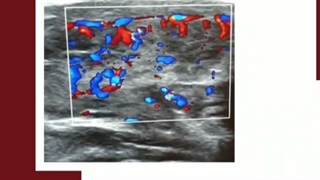

سونوگرافی کالر داپلر یکی از محبوب‌ترین و پرکاربردترین روش‌های سونوگرافی است که عمدتاً برای بررسی غیرتهاجمی وضعیت عروق و وریدهای اصلی نواحی گردن، بازوها و پاهای بیماران استفاده می‌شود. در واقع کمک می‌کند تا پزشک متوجه شود که آیا جریان خون در این نواحی کُند یا در قسمتی از وریدها یا شریان‌ها متوقف شده است یا خیر.

سونوگرافی داپلر با همان دستگاه سونوگرافی معمولی انجام می‌شود و معمولاً در سه ماهه سوم بارداری در زنانی که حاملگی‌های پرخطر دارند؛ استفاده می‌شود. زیرا به کمک امواج صوتی منعکس‌شده امکان تعیین سرعت و جهت جریان خون و ضربان قلب جنین وجود دارد. به همین دلیل در بررسی رشد طبیعی جنین و دریافت مناسب خون و مواد مغذی توسط بافت‌ها مفید است. در ادامه به جزئیات بیشتری از سونوگرافی داپلر در دوران بارداری اشاره خواهیم کرد.